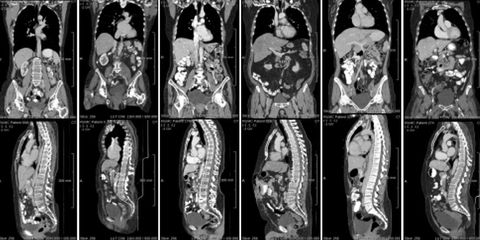

Annotation of whole-body lesions in CT across multiple timepoints

Evaluation of multi-organ CT registration models for lesion tracking across timepoints